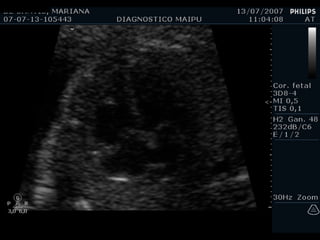

ECOCARDIOGRAFIA FETAL Modo B Modo M Doppler ¿CUANDO? A partir de la sem 12 por vía TV A partir de la sem 18 por vía abdominal Optimo: semana 22

Evaluación del corazón fetal en la ecografía obstétrica Modo B ¿CUANDO? Segundo y tercer trimestres ¿Como? De mayor a menor

EXAMEN BASICO GENERAL Ubicación Eje Tamaño  Cámaras Pericardio Ritmo VALVULAS AV Apertura y movimiento Inserción AURICULAS Tamaños Flap del foramen oval Septum VENTRICULOS Tamaños Paredes Banda moderadora Tabique

EXAMEN BASICO VENTRICULOS Tamaños Paredes Banda moderadora Tabique